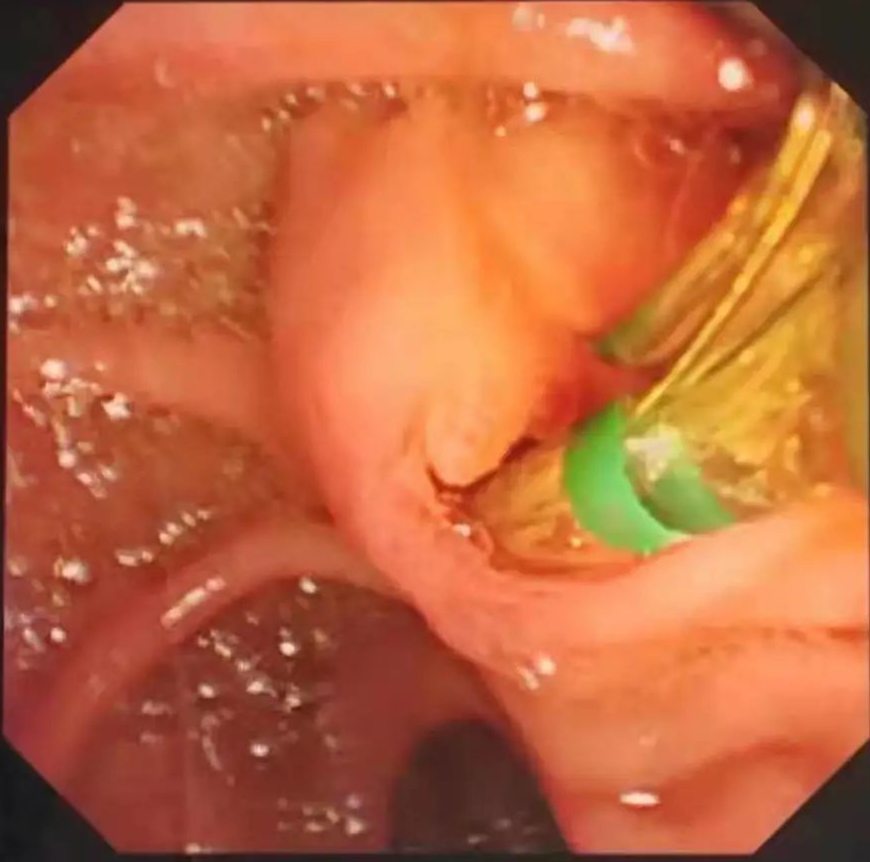

消化内科邱春雷主任与陈敬成副主任医师会诊后,与普外科张旭华主任、黄无浪主治医师及患者家属协商决定:为患者实行局麻内镜下逆行胰胆管造影(ERCP)+十二指肠乳头肌切开(EST)取石术+鼻胆管引流术(ENBD)。患者手术顺利,术中胆总管可见多个直径约0.6cm结石及胆泥,解除了胆总管梗阻,术后患者康复良好,腹痛、腹胀等症状缓解。

专家解说:ERCP作为一项高新技术,属国家四级手术范畴,是内镜专家公认的技术难度高、操作复杂的内镜技术,被誉为内镜技术“皇冠上的明珠”。(文图:陈敬成 审核:邱春雷 周臻 彭晓露)